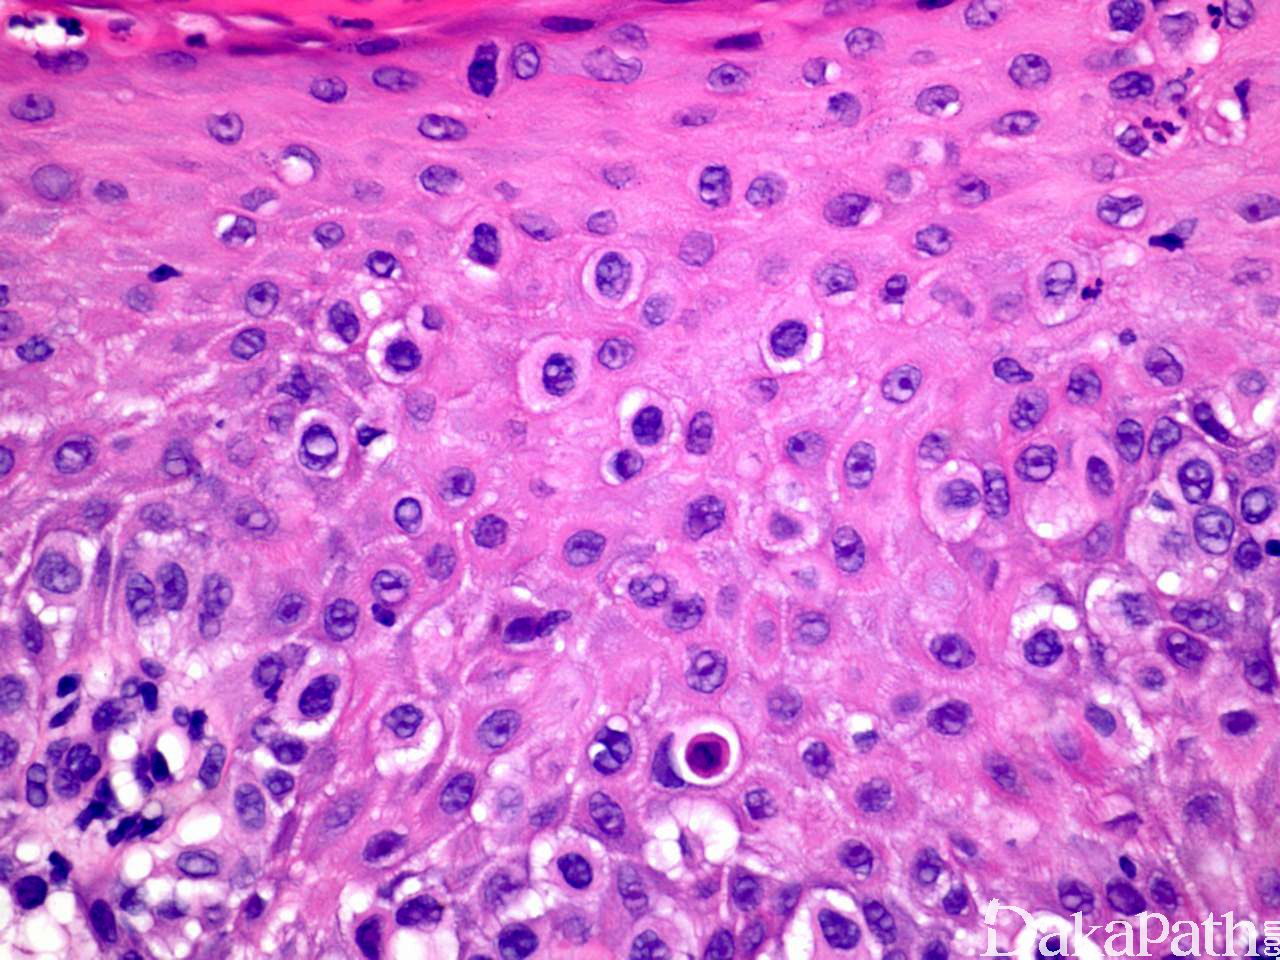

组织学特征性地表现为表皮内非典型上皮细胞单个散在或成群分布于上皮各层内,有时可形成导管或腺样结构;

细胞体积大,胞质淡染、内含黏液或透亮,有时可伴有黑色素颗粒;

Paget 细胞间常见裂隙样结构;